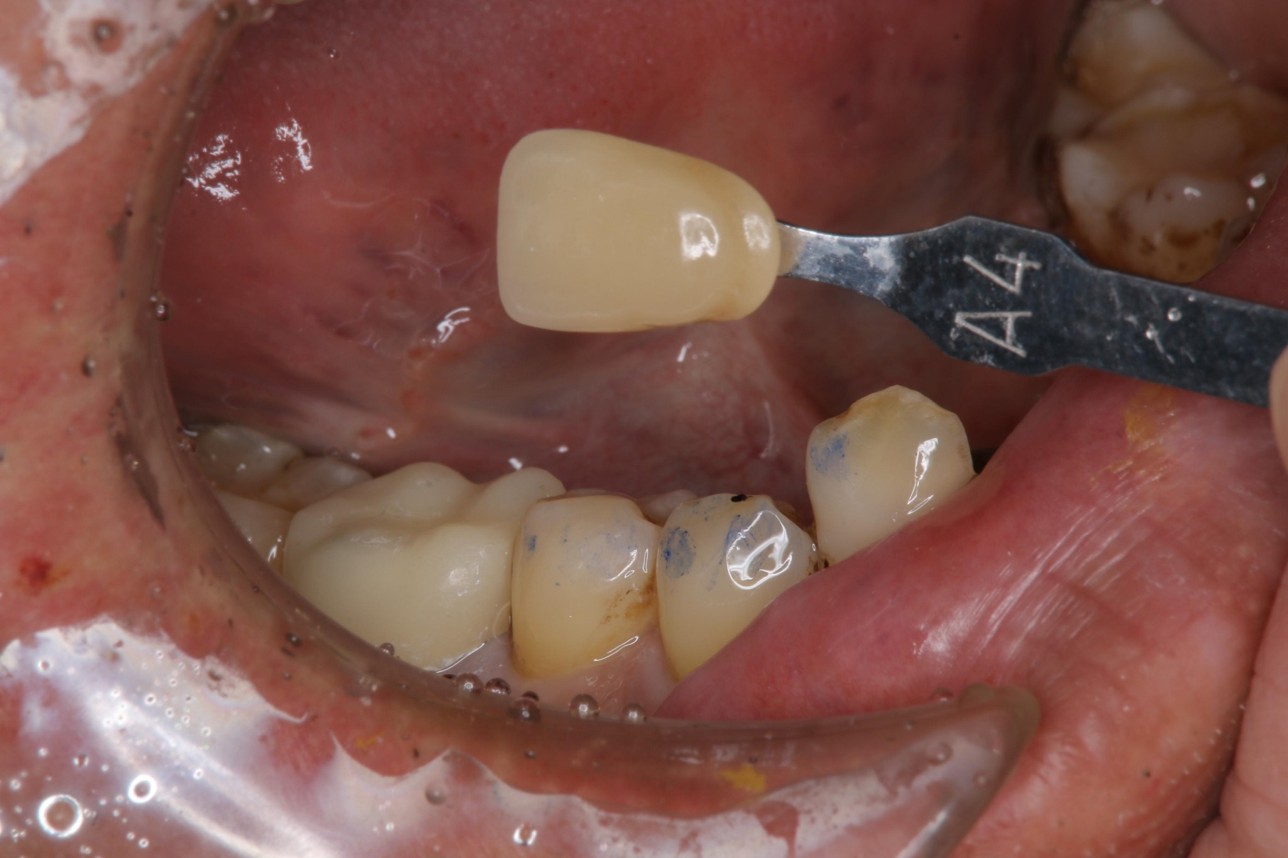

照相比色